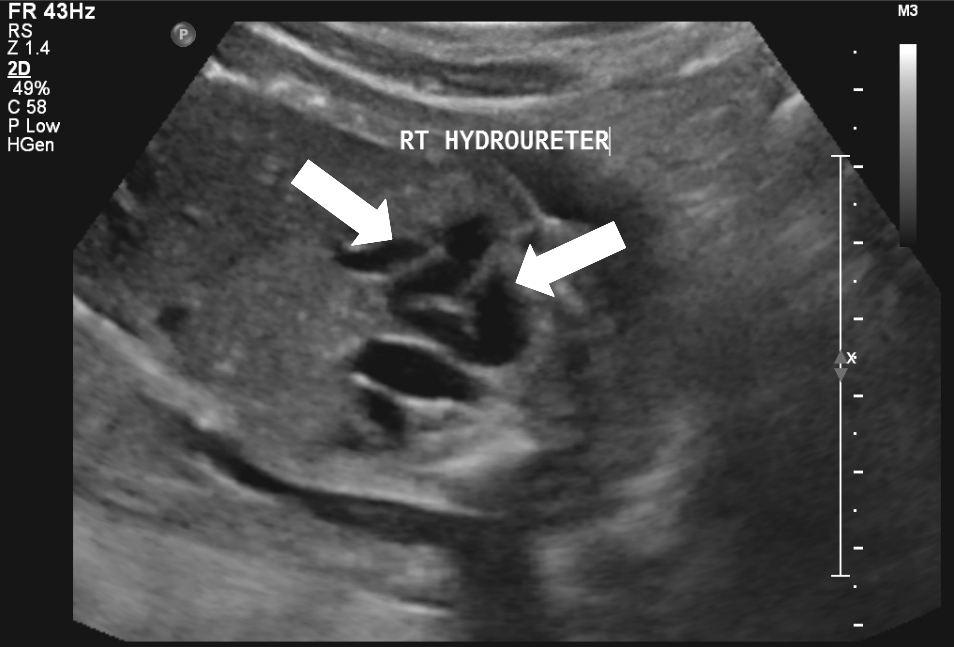

Diagnose vóór de geboorte

Veel ernstige vormen van urethrakleppen worden al gezien bij echografisch onderzoek vóór de geboorte. Bij de 20 weken echo (of misschien in de toekomst bij een 13 weken echo) worden verwijde nierbekkens en urineleiders gezien. De blaas kan dikwandig zijn, maar ook zeer groot en uitgerekt. Vaak kan het verwijde deel van de plasbuis ónder de blaas worden gezien. Dat noemen we het “sleutelgat teken” omdat de blaas in lengtedoorsnede op de echo er dan uitziet als een sleutelgat. De hoeveelheid vruchtwater kan normaal of verminderd zijn. Als er een verdenking is op urethrakleppen wordt de bevalling gedaan in een centrum waar direct optimale zorg kan worden geleverd aan de pasgeborene.

20 weken echografie: links: dikwandige blaas met verwijding van de plasbuis tot aan de kleppen (pijl): het “sleutelgat teken”. Onder: verwijde urineleiders. Bij kinderen gaan de urineleiders bij verwijding ook erg gekronkeld verlopen.